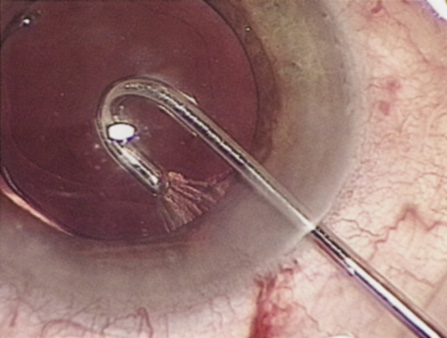

Hydrodissection can be performed after the surgeon has successfully completed capsulorrhexis.97 If the capsulorrhexis is not intact, fluid forced around the interior of the capsule may cause the bag to splay open. With capsulorrhexis, hydrodissection is a safe and extremely useful maneuver. Hydrodissection can be thought of as two maneuvers: hydrodelineation and cortical cleaving hydrodissection. By placing a 27-gauge cannula on a syringe filled with balanced saline solution (BSS), the surgeon can direct fluid beneath the residual anterior capsular rim to create a cleavage plane. Depending on the direction the fluid wave takes, different lamellae of the cataract will be separated. Hydrodelineation is the term used when the cleavage plane separates the adult nucleus from the fetal nucleus or the adult nucleus from the more peripheral epinucleus. Hydrodelineation often results in the characteristic golden ring sign (Fig. 11). Cortical cleavage occurs when the cortex is separated from the capsular bag (Fig. 12). Finding the cortical cleavage plane may be facilitated by gently lifting the capsular margin away from the cortex with the BSS cannula before injecting. Several small bursts of fluid allow the surgeon to monitor progress of the fluid wave. When dealing with a soft nucleus, the authors strive to perform true cortical cleaving hydrodissection. For a hard nucleus, hydrodelineation allows manipulation of less of the nuclear bulk, although the remaining epinuclear shell must be addressed in an additional step. Hydrodelineation is particularly useful if the nucleus is not freely mobile after cortical cleaving hydrodissection.

Fig. 11. A crisp “golden ring” is seen from the fluid cleft between the epinucleus and nucleus with hydrodelineation.

Fig. 12. Hydrodissection, performed subincisionally with a 27-gauge J-cannula, produces a cleavage plane between the capsule and the cortex. The small blue arrows indicate the advancing fluid wave.